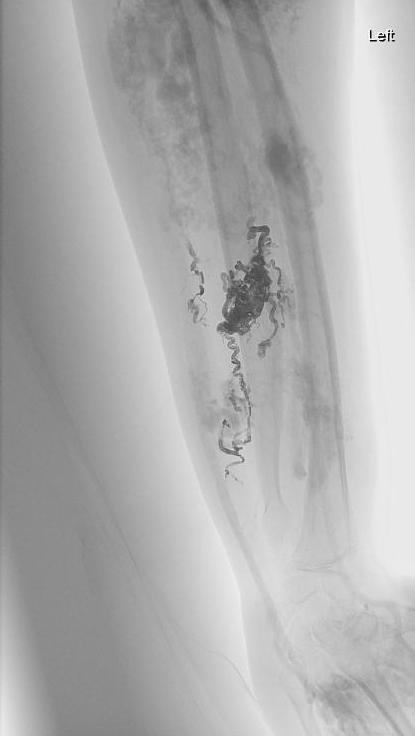

Onyx 胶在肢体血管畸形方面的应用

2年以后腕和前臂不适症状复发

两年后复查

腕部AVM再栓塞